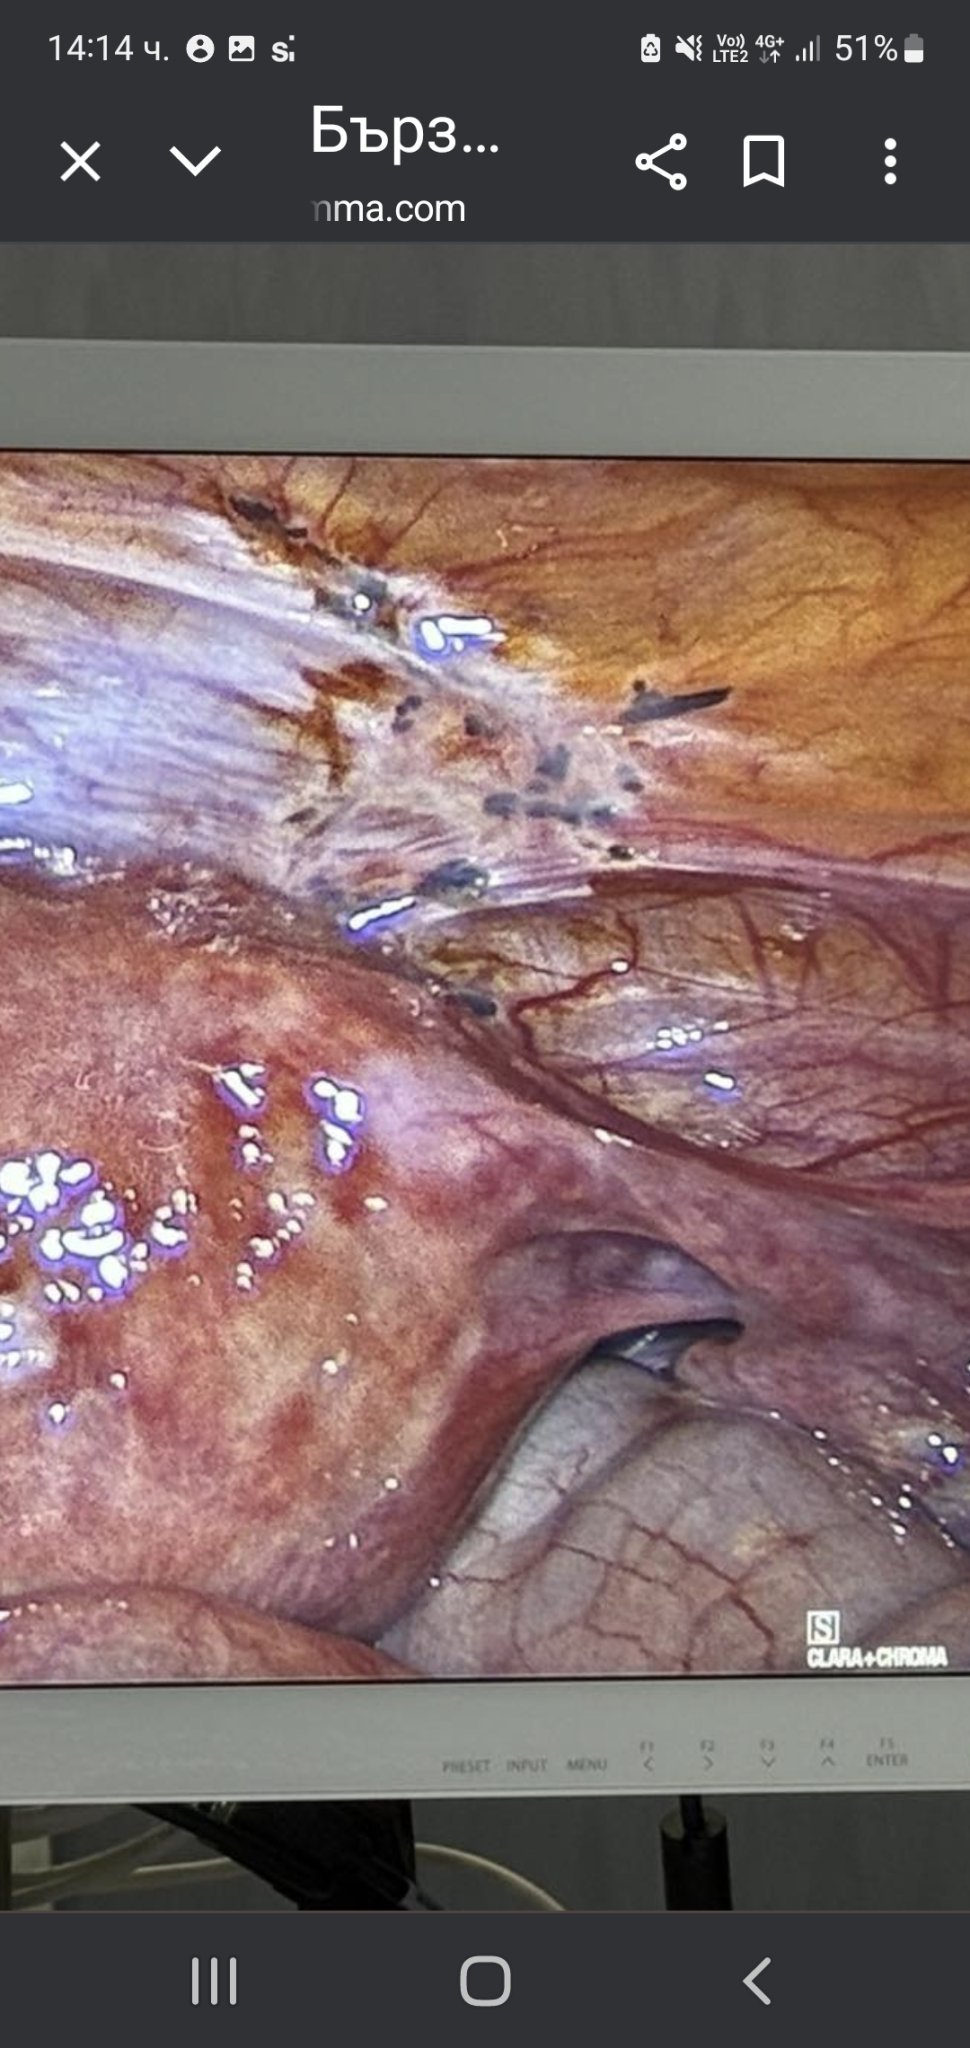

При лапароскопска операция за апендикса на дъщеря ми откриха тези тъмни петна по матката..Взет е материал за биопсия.Дали да се притеснявам за нещо лошо?

Къде са тъмните петна? Не мога да се ориентирам.

Ето ги

Аз не бих се притеснявала, ще чакам да излязат резултати. Винаги така постъпвам, не се тръшкам предварително и не мисля. Вкл. и когато правиха биопсия на възел на щитовидната на дъщеря ми, както и за куп други проблеми.